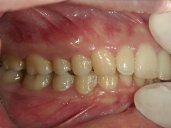

矯正歯科 治療前 右

矯正歯科 治療後 右